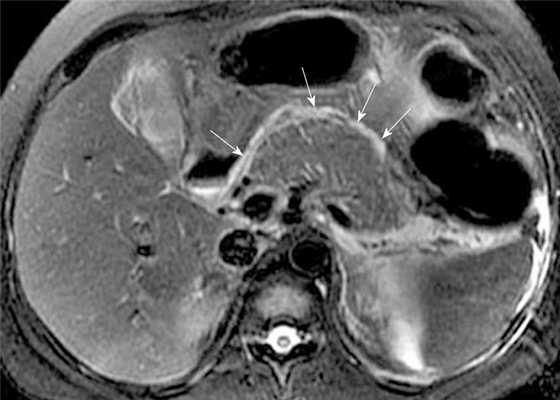

МРТ поджлудочной железы. МР-признаки острого панкреатита: отек, жидкость в парапанкреатической клетчатке. Некроз поджелудочной железы.

Для оценки некроза поджелудочной железы может быть использовано болюсное введение контрастных препаратов гадолиния. Качество визуализации верхних отделов брюшной полости дополнительно улучшается с использованием поверхностных катушек с фазированной решеткой и методов подавления сигнала от жировой ткани.

Картина морфологических изменений острого панкреатита на КТ и МРТ схожа.

Поджелудочная железа может быть увеличена локально (обычно головка поджелудочной железы) или диффузно. Острые воспалительные изменения проявляются в виде нитей низкой интенсивности сигнала в окружающей перипанкреатической клетчатке.

Также могут быть выявлены осложнения острого панкреатита. Кровоизлияния характеризуются укорочением Т1 или высокой интенсивностью сигнала на T1-взвешенных последовательностях с подавлением сигнала от жировой ткани. Скопление жидкости в перипанкреатическом пространстве, псевдокисты и абсцессы распознаются по их высокой интенсивности сигнала на T2-взвешенных последовательностях. Деваскуляризованные или некротические участки поджелудочной железы не дают усиления при динамических изображениях с гадолинием. МРТ также может превосходить КТ при обнаружении областей стерильного некроза поджелудочной железы, которые выглядят на КТ как псевдоксисты.

МРТ эквивалентно КТ-сканированию в оценке локализации и степени воспалительных изменений перипанкреатических тканей и скоплений жидкости. Кроме того, МРТ оказалась эквивалентной при оценке степени некроза поджелудочной железы. Chalmers и др. установили, что МРТ более информативно, чем КТ, при определении характера скоплений жидкости и визуализации желчных камней.